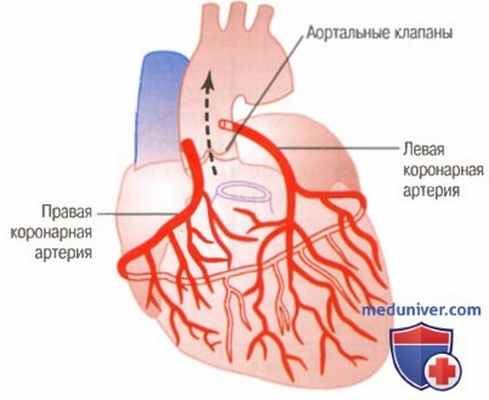

Анатомия коронарных артерий: КТ-изображения